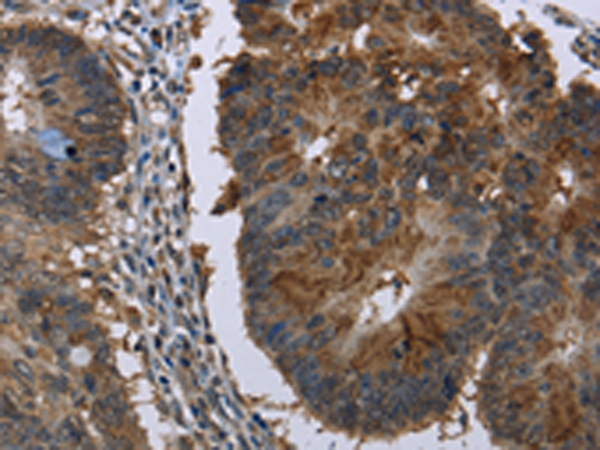

分类: 科研抗体货号: P01378别名: SLIM2应用: WB,IHC反应种属: Human, Mouse

分类: 科研抗体货号: P01441别名: RNMX; HNRPG; HNRNPG; RBMXP1; RBMXRT; hnRNP-G应用: WB,IHC反应种属: Human, Mouse, Rat

分类: 科研抗体货号: P01373别名: FHFR; FGFR5应用: WB,IHC反应种属: Human, Mouse, Rat

分类: 科研抗体货号: P01433别名: HL; HTGL; LIPH; HDLCQ12应用: WB,IHC反应种属: Human, Mouse

分类: 科研抗体货号: P01458别名: CBAS1; PFIC4; SDR11E3应用: IHC反应种属: Human, Mouse, Rat

分类: 科研抗体货号: P01432别名: HCCR; HCCR1; HCCR2; HCCR-1; HCCR-2; HCRR-2; SLC55A3; 1110019O13Rik应用: WB,IHC反应种属: Human, Mouse

分类: 科研抗体货号: P01454别名: HSE; RODH; SDR9C6应用: WB,IHC反应种属: Human, Mouse

分类: 科研抗体货号: P01426别名: CSA; MOT; MOT2; GRP75; PBP74; GRP-75; HSPA9B; MTHSP75; HEL-S-124m应用: WB,IHC反应种属: Human, Mouse, Rat

分类: 科研抗体货号: P01425别名: GPRK5; FP2025应用: IHC反应种属: Human, Mouse, Rat